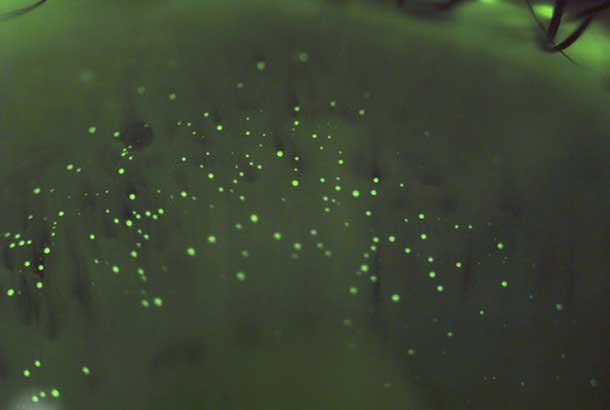

"name": "Blebs (Endothelial)",

"detail": "<p>Endothelial edema</p>\n\n<h2>Symptoms</h2>\n\n<ul>\n\t<li>None</li>\n</ul>\n\n<h2>Signs</h2>\n\n<ul>\n\t<li>Black spots which appear to be &ldquo;holes&rdquo; on endothelium when viewed with specular reflection</li>\n\t<li>Intracellular edema of endothelial cells</li>\n\t<li>Maximum response occurs 10-20 minutes after lens insertion.</li>\n\t<li>Reduction in response occurs over initial weeks of lens wear.</li>\n</ul>\n\n<h2>Etiology</h2>\n\n<ul>\n\t<li>Local decrease in pH, associated with hypoxia and carbon dioxide build-up</li>\n\t<li>Typically occurs in unadapted wearers. Degree related to oxygen transmissibility of the lens material</li>\n</ul>\n\n<h2>Prevalence</h2>\n\n<ul>\n\t<li>Occasional</li>\n</ul>\n\n<h2>Differential Diagnosis</h2>\n\n<ul>\n\t<li><a href=\"/condition/62/\">Guttata</a></li>\n\t<li>See: <a href=\"/condition/62/\">Endothelial Changes &ndash; Differential Diagnosis</a></li>\n</ul>\n\n<h2>Management</h2>\n\n<ul>\n\t<li>No action required</li>\n\t<li>May consider refit into SiHy or high Dk GP lenses if response is severe</li>\n</ul>",